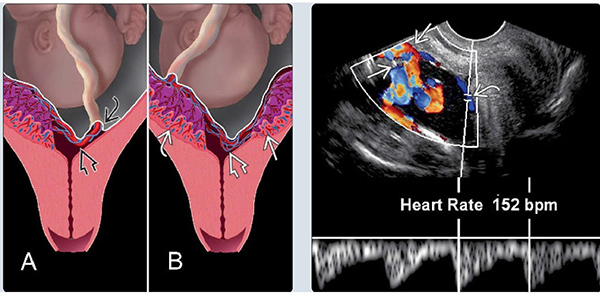

Bản chất của biến chứng này là hiện tượng các mạch máu cuống rốn của thai nhi chạy ngang qua hoặc nằm gần với lỗ mở của cổ tử cung, nó nằm trong màng, không được bảo vệ. Một khi các mạch máu này bị vỡ thì bạn sẽ mất máu nghiêm trọng, ảnh hưởng đến tính mạng của mẹ và thai nhi.

Nếu chịu khó tìm hiểu về kiến thức sinh sản mẹ sẽ biết rằng vốn dĩ mạch máu nuôi thai được bảo vệ bởi chất thạch Wharton nằm trong dây rốn như mạch máu tiền đạo thì không. Mạch máu nuôi thai không có chất thạch nâng đỡ, trong nhiều trường hợp nó còn dính chặt vào lớp màng đệm bên trên nên dễ bị rách khi vỡ ối, bấm ối. Lượng máu chảy ra là máu của thai nhi nên tình trạng bị mất mạng là điều không thể tránh khỏi.

Theo lý giải từ phía các bác sĩ chuyên khoa thì biến trứng này có thể gây ra bởi hiện tượng sa dây rốn, tức là dây rốn đi vào màng nên mạch máu không được nhau thai bảo vệ. Ngoài ra việc nhau thai chia làm 2 mảnh cũng khiến mạch máu bị hở ra ở nơi giao nhau giữa 2 thùy, tạo nên mạch máu tiền đạo.

Lúc này bác sĩ sẽ sử dụng phương pháp siêu âm đầu dò kết hợp với siêu âm Doppler để chẩn đoán sớm và đưa ra các biện pháp điều trị kịp thời. Thực chất thì những thai phụ được chẩn đoán có nhau cài răng hoặc thuộc nhóm đối tượng có nguy cơ cao sẽ được tiến hành xét nghiệm.